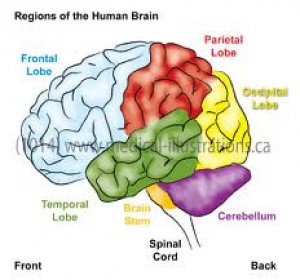

Seperti yg dikatakan tim dokterku di San San Fransisco, area perdarahan ku adalah di pariental lobe, yg mana :

1.1. Primary and secondary somatosensory.

2.2. Postcentral and supramarginal gyrus.

3.3. Angular gyrus.

Gambar sebelah kiri adalah otak kiri, karena pariental lobe ada juga di sebelah kana otak kanan. Gambar di sebelah kanan, adalah pembagian area yg terkenasensorik utama ( primary somatosensory ).